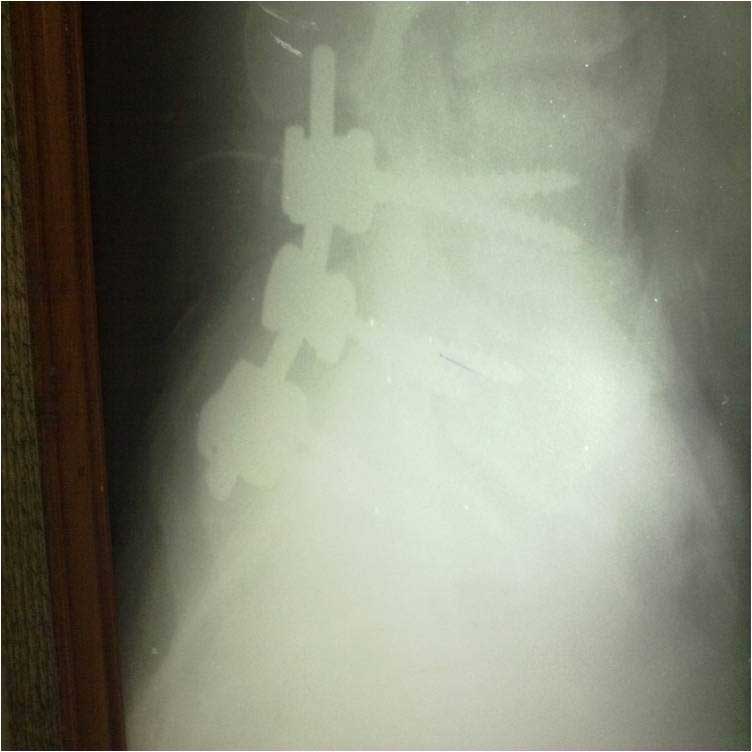

post op L5 S1 FIXATION

Spine Fixation Lumbar Spine

• Spine Fixation Lumbar Spine